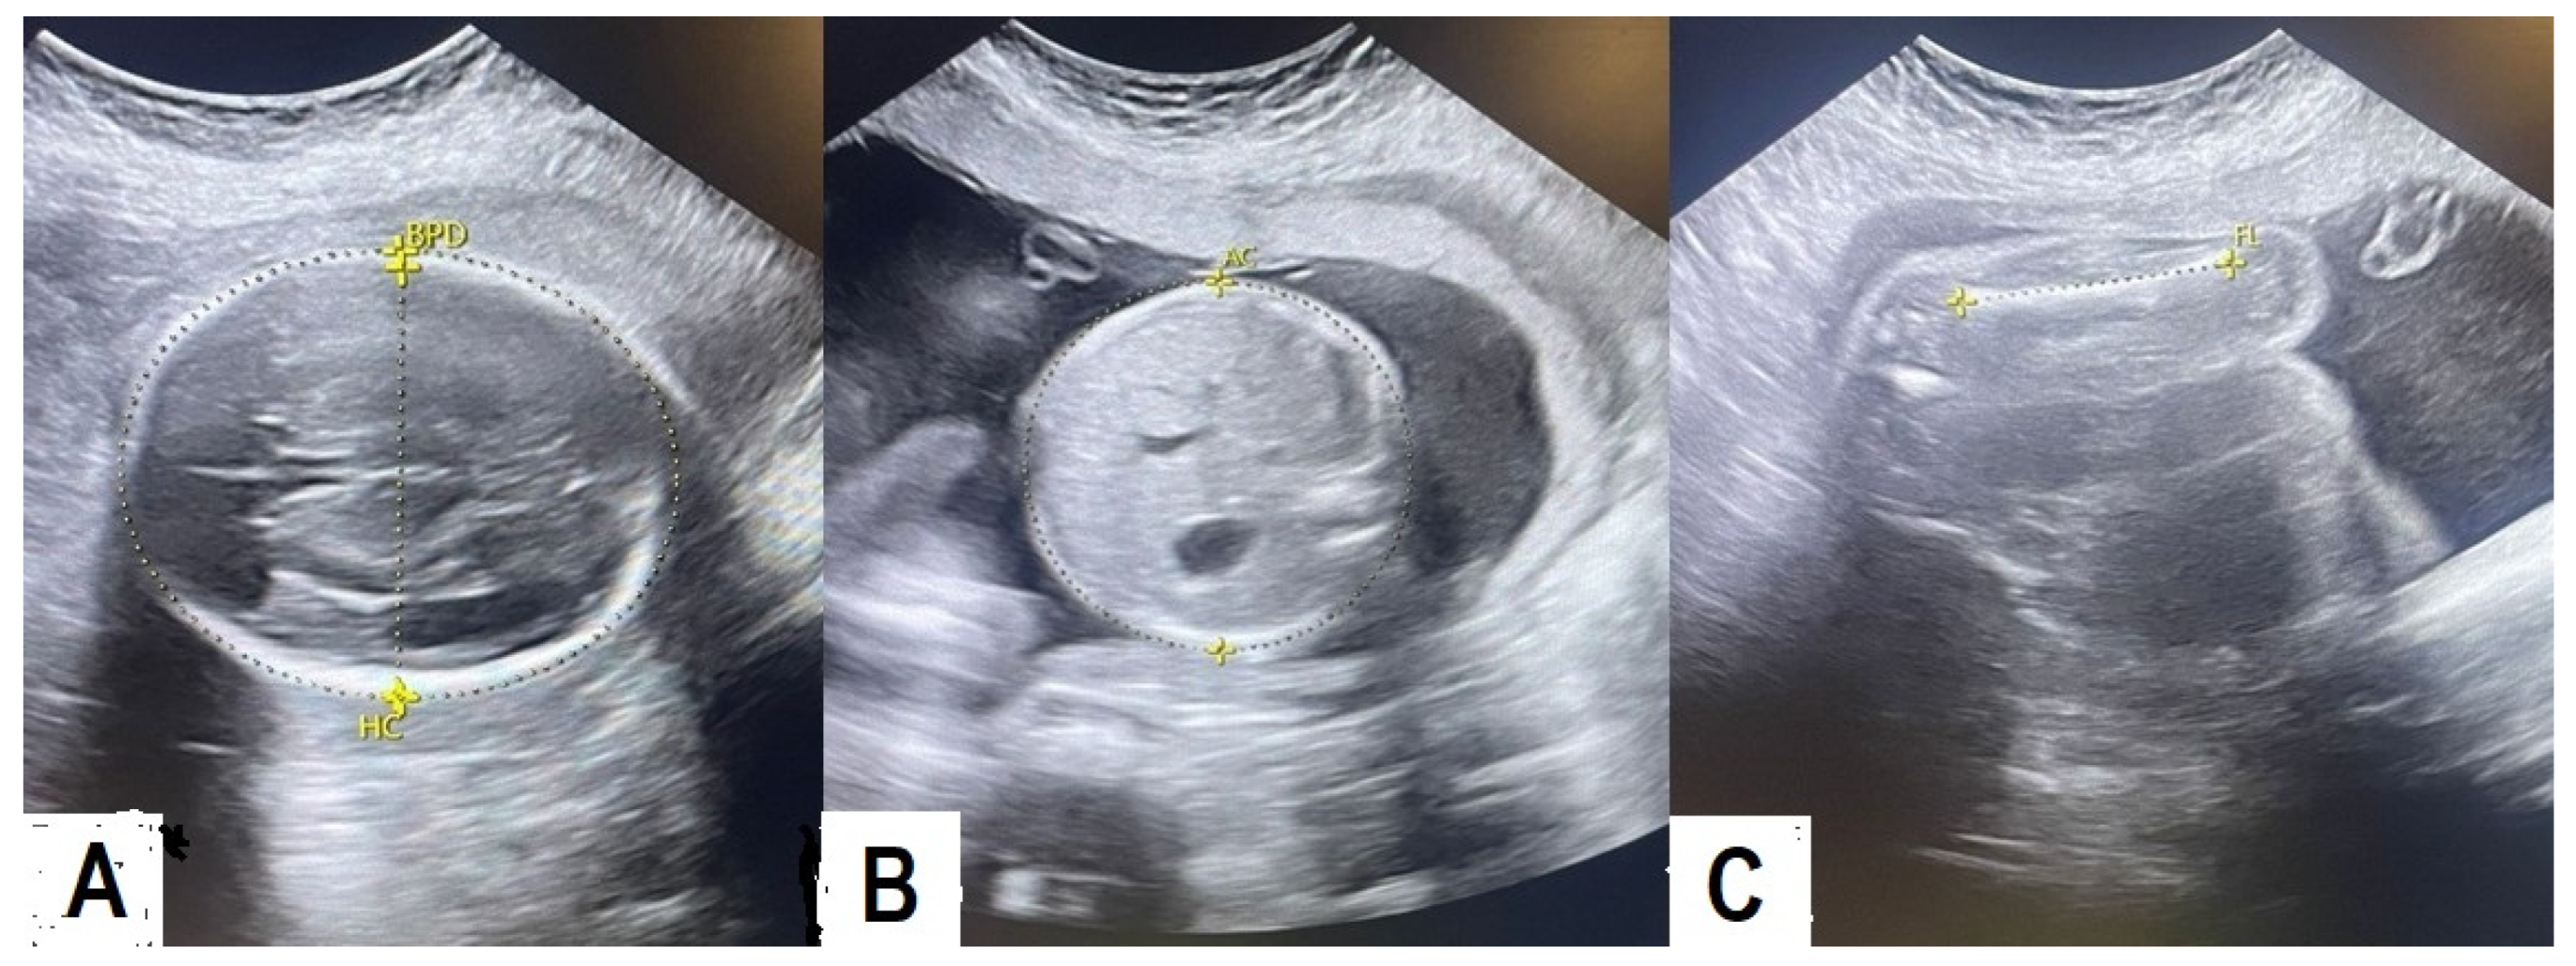

2.2. Procedure for EFW

| HC | Head circumference |

| AC | Abdominal circumference |

| FL | Femur length |